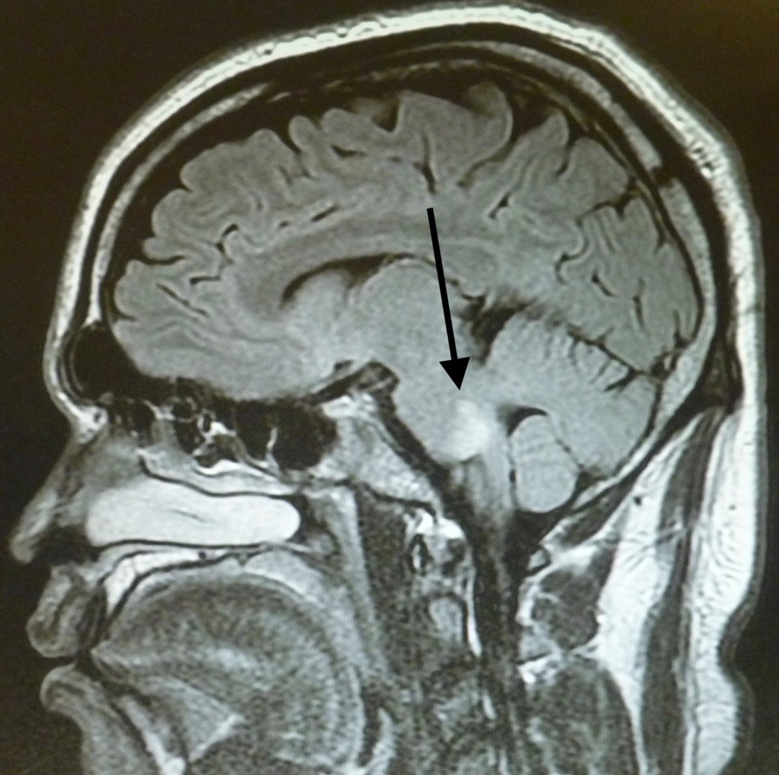

MRI of the brain repeated 4 days later showed no change in the signal abnormalities involving the left centrum semiovale and left periatrial white matter. Abnormal signal involving the pons bilaterally was demonstrated (Figures 3 and 4). Findings of MRI of the cervical and thoracic spines were normal.

Figure 4. MRI scans 4 days later showed abnormal signal involving the pons.